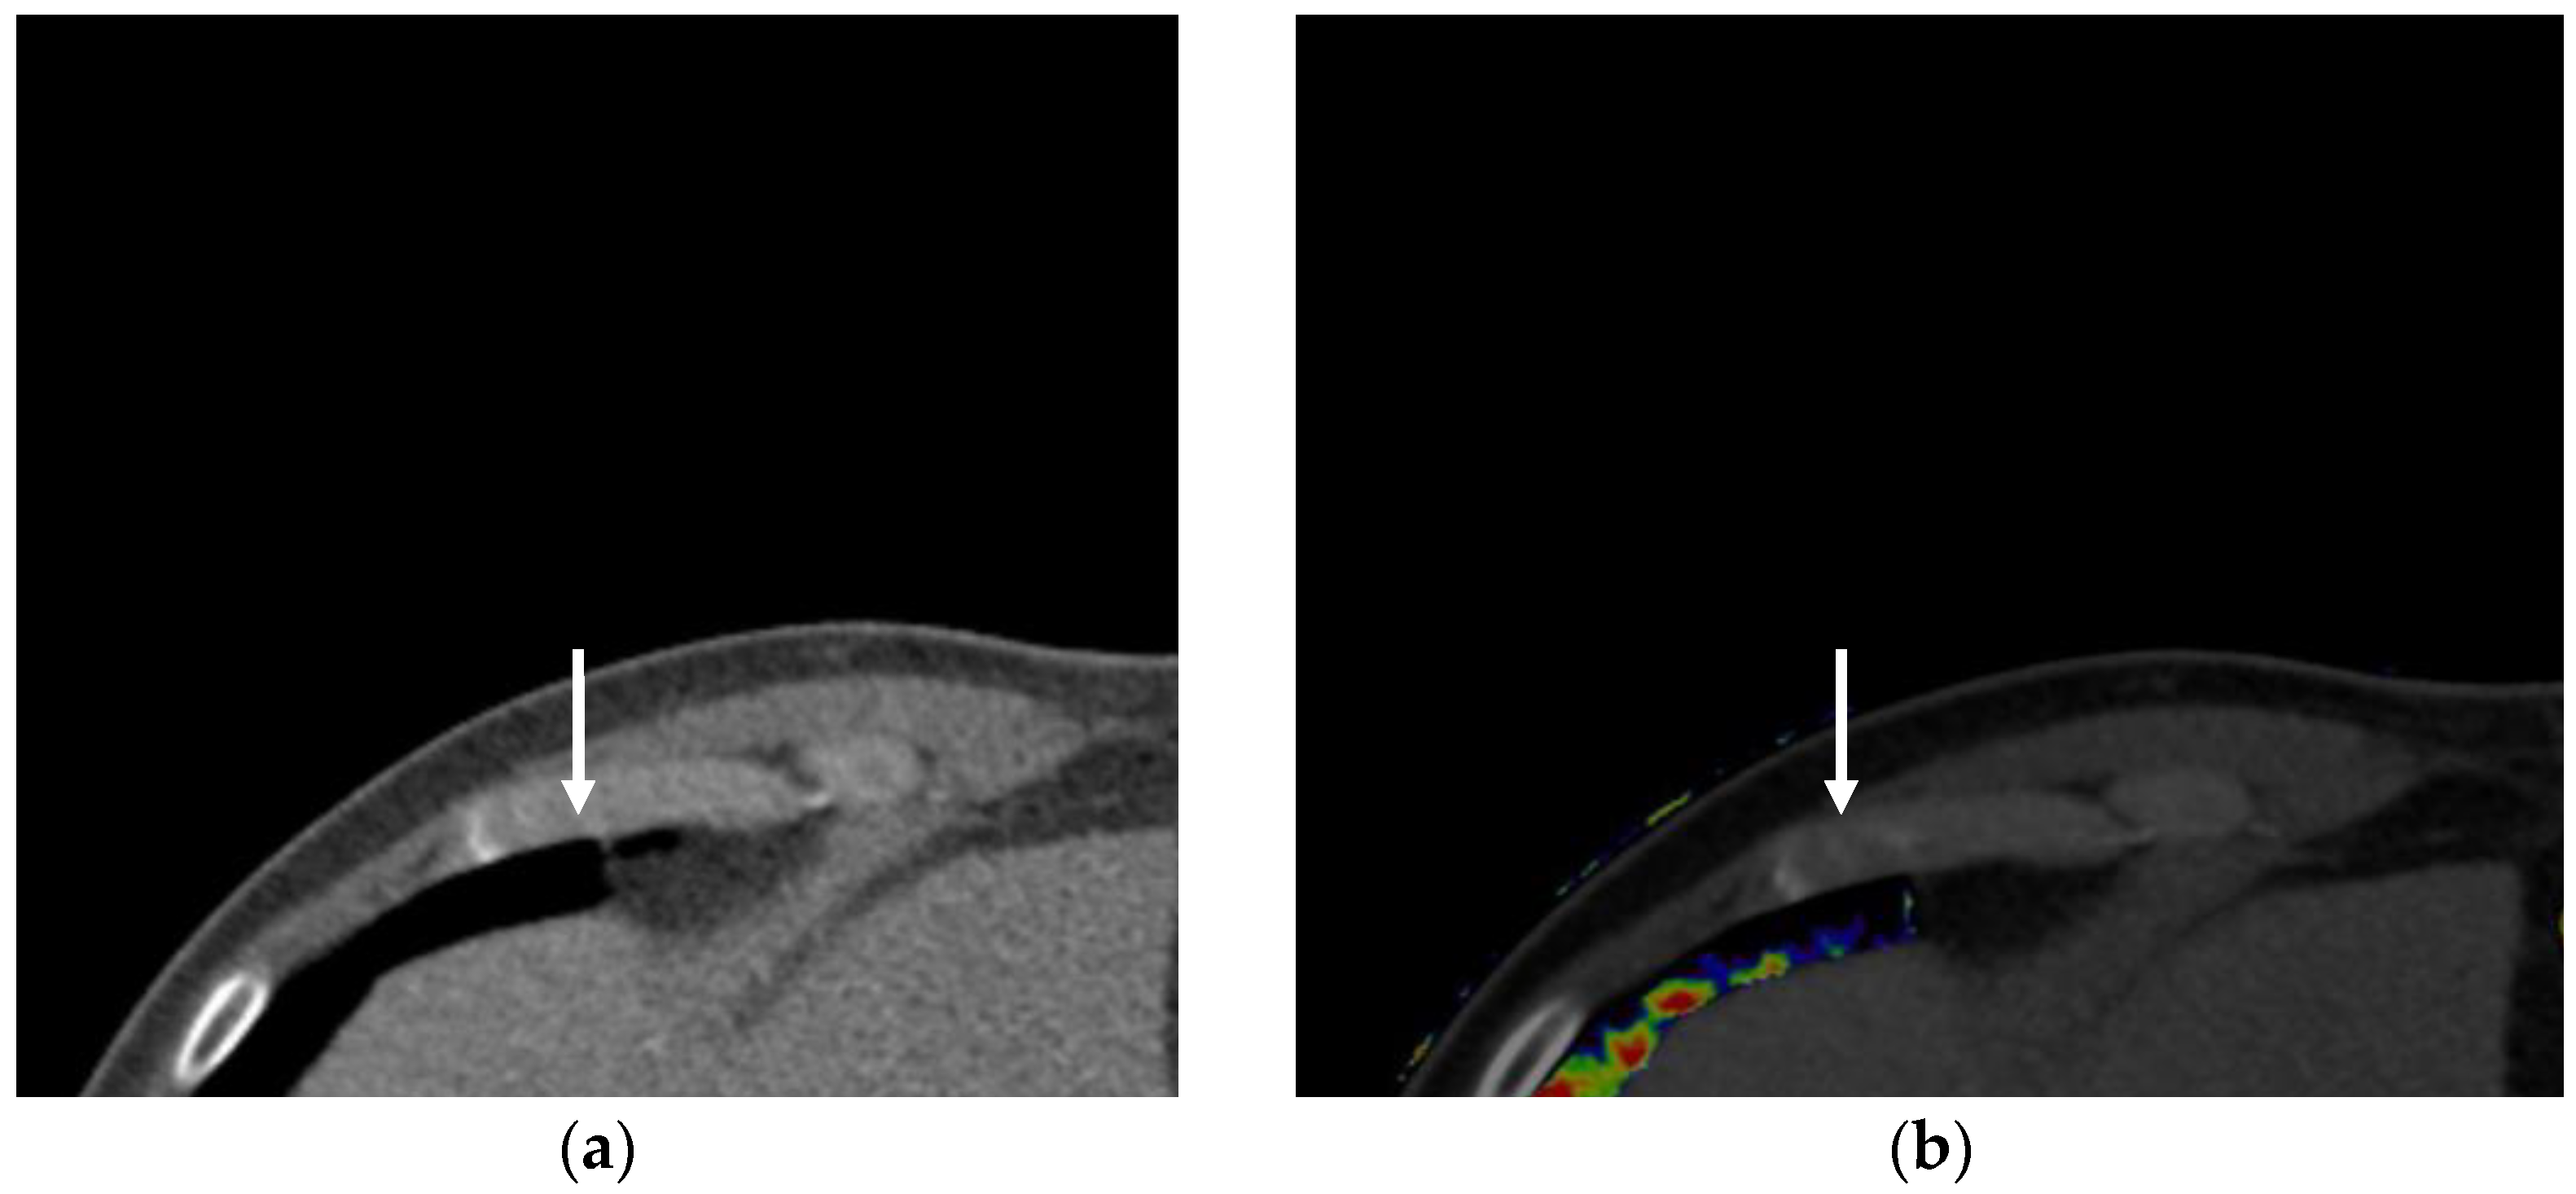

3.1.2. Virtual Monochromatic Imaging

- Dane, B.; Patel, H.; O’Donnell, T.; Girvin, F.; Brusca-Augello, G.; Alpert, J.B.; Niu, B.; Attia, M.; Babb, J.; Ko, J.P. Image Quality on Dual-energy CTPA Virtual Monoenergetic Images: Quantitative and Qualitative Assessment. Acad. Radiol. 2018, 25, 1075–1086. [Google Scholar] [CrossRef] [PubMed]

- Bae, K.; Jeon, K.N.; Cho, S.B.; Park, S.E.; Moon, J.I.; Baek, H.J.; Choi, B.H. Improved Opacification of a Suboptimally Enhanced Pulmonary Artery in Chest CT: Experience Using a Dual-Layer Detector Spectral CT. AJR Am. J. Roentgenol. 2018, 210, 734–741. [Google Scholar] [CrossRef] [PubMed]

- D’Angelo, T.; Cicero, G.; Mazziotti, S.; Ascenti, G.; Albrecht, M.H.; Martin, S.S.; Othman, A.E.; Vogl, T.J.; Wichmann, J.L. Dual energy computed tomography virtual monoenergetic imaging: Technique and clinical applications. Br. J. Radiol. 2019, 92, 20180546. [Google Scholar] [CrossRef]

- Ohana, M.; Jeung, M.Y.; Labani, A.; El Ghannudi, S.; Roy, C. Thoracic dual energy CT: Acquisition protocols, current applications and future developments. Diagn. Interv. Imaging 2014, 95, 1017–1026. [Google Scholar] [CrossRef]

- D’Angelo, T.; Bucher, A.M.; Lenga, L.; Arendt, C.T.; Peterke, J.L.; Caruso, D.; Mazziotti, S.; Blandino, A.; Ascenti, G.; Othman, A.E.; et al. Optimisation of window settings for traditional and noise-optimised virtual monoenergetic imaging in dual-energy computed tomography pulmonary angiography. Eur. Radiol. 2018, 28, 1393–1401. [Google Scholar] [CrossRef]

- Wittram, C.; Maher, M.M.; Yoo, A.J.; Kalra, M.K.; Shepard, J.A.; McLoud, T.C. CT angiography of pulmonary embolism: Diagnostic criteria and causes of misdiagnosis. Radiographics 2004, 24, 1219–1238. [Google Scholar] [CrossRef]

- Ozawa, Y.; Hara, M.; Shibamoto, Y. The frequency of insufficient contrast enhancement of the pulmonary artery in routine contrast-enhanced chest CT and its improvement with an increased injection rate: A prospective study. J. Thorac. Imaging 2011, 26, 42–47. [Google Scholar] [CrossRef] [PubMed]